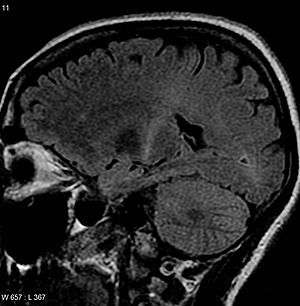

An MRI with increased signal in the posterior part of the internal capsule which can be tracked to the motor cortex consistent with the diagnosis of ALS | |

Because symptoms of ALS can be similar to those of a wide variety of other, more treatable diseases or disorders, appropriate tests must be conducted to exclude the possibility of other conditions.[1] One of these tests is electromyography (EMG), a special recording technique that detects electrical activity in muscles.[1] Certain EMG findings can support the diagnosis of ALS.[1] Another common test measures nerve conduction velocity (NCV).[1] Specific abnormalities in the NCV results may suggest, for example, that the person has a form of peripheral neuropathy (damage to peripheral nerves) or myopathy (muscle disease) rather than ALS. While a magnetic resonance imaging (MRI) is often normal in people with early stage ALS, they can reveal evidence of other problems that may be causing the symptoms, such as a spinal cord tumor, multiple sclerosis, a herniated disk in the neck, syringomyelia, or cervical spondylosis.[1]